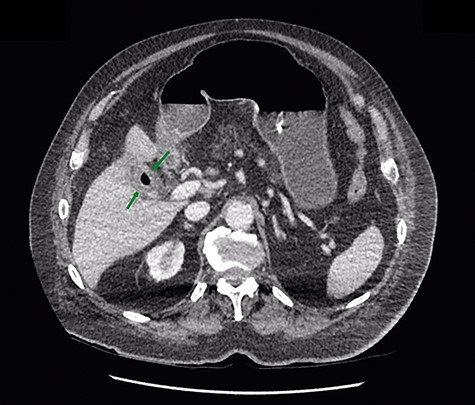

Given that the patient was clinically well, he was managed conservatively overnight with a nasogastric tube and intravenous fluid therapy. The CT scan was closely reviewed by the surgical team the following day and noted the presence of gas within the gallbladder, which was not commented upon by the radiologist (Fig. 2). Furthermore, SBO transition point appeared to be in the distal ileum, where a 3-cm “soft tissue” mass was seen (Fig. 3). His previous CT scan that diagnosed his chronic cholecystitis demonstrated a 3-cm gallstone within the gallbladder, which was not seen on the current CT. The findings of gas within the gallbladder in the setting of SBO and a mass of similar size to the known gallstone raised the suspicion for gallstone ileus. The patient then underwent a laparotomy and enterotomy for a 43-mm gallstone impacted in the distal ileum (Fig. 4). Apart from an episode of ileus, he made a full recovery post-operatively and was discharged home, with an outpatient follow-up in the surgical clinic.

In this scenario, this patient was known to have gallstones and a virgin abdomen, so gallstone ileus was always a possibility. It was the finding of gas in the gallbladder on CT that prompted the surgeons to consider the diagnosis. It is important to note that the diagnosis of gallstone ileus could not be made on plain abdominal radiography, despite the fact that the X-ray was consistent with SBO. This is due to very little air in the biliary tree and only a small bubble in the gallbladder. The gallstone was not calcified and appears of soft tissue density, and was invisible on plain X-ray. Therefore, CT abdomen should be the investigation of choice for suspected gallstone ileus, due to superior sensitivity of CT to detect small amount of gas within the biliary tree and to identify an intra-luminal foreign body of soft tissue density. Neither of these things is possible with plain radiology.